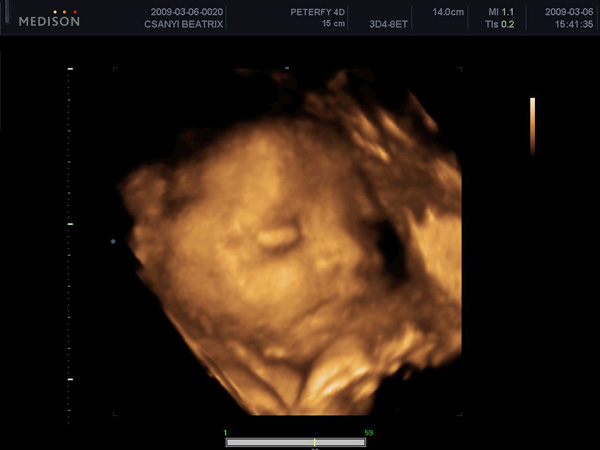

trixi nagyon édes kicsi fiad az uh. képen :)